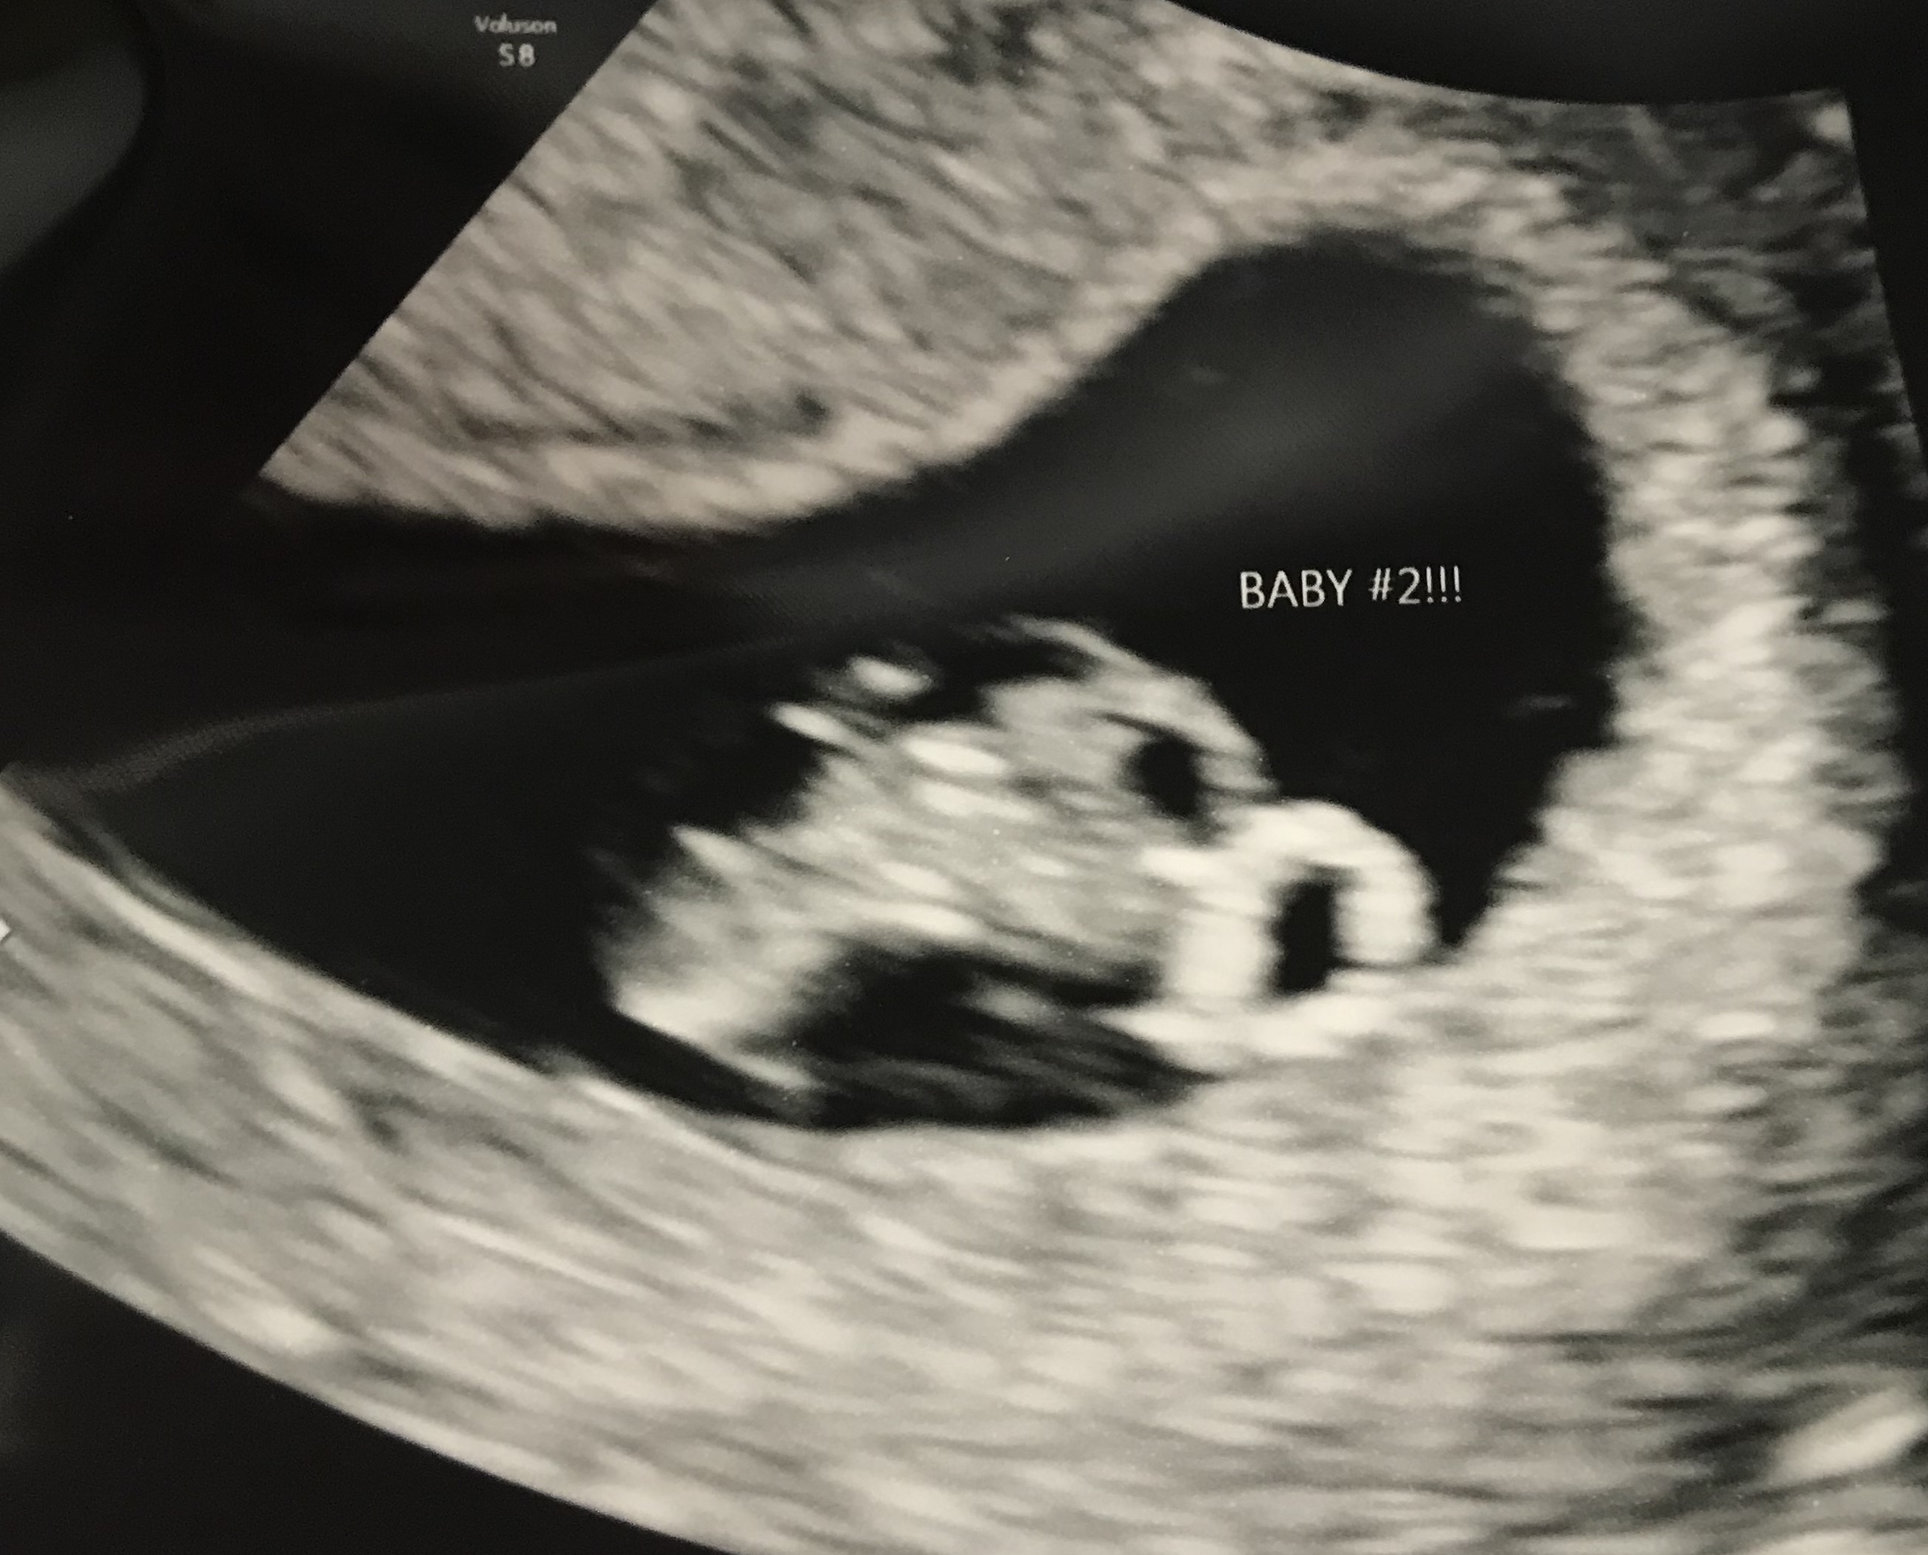

Still so tiny and on the yolk sac, but we got to see our sweet baby’s heartbeat today! Dr said the heartbeat was around 150. Such a huge relief since I was worrying about my lack of symptoms a couple of days ago! Baby is basically right on track with my last period. They said he/she was measuring at 6 weeks 3 days, but are staying with 6 weeks and due date of May 22nd. All the feels today! ❤️